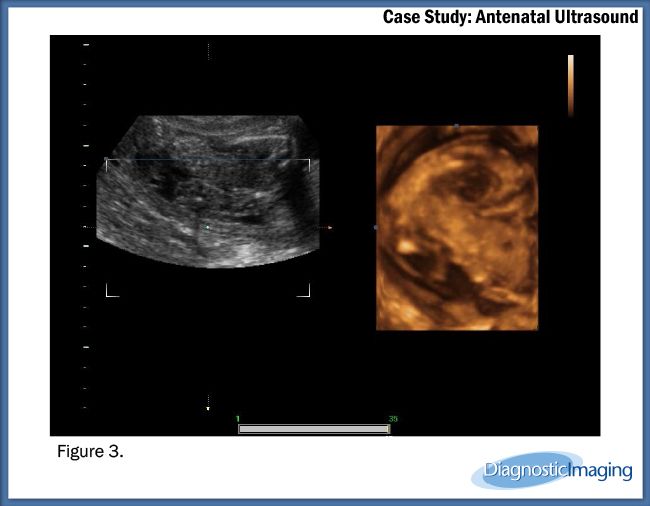

Case History: 25-year-old patient presents for antenatal ultrasound.